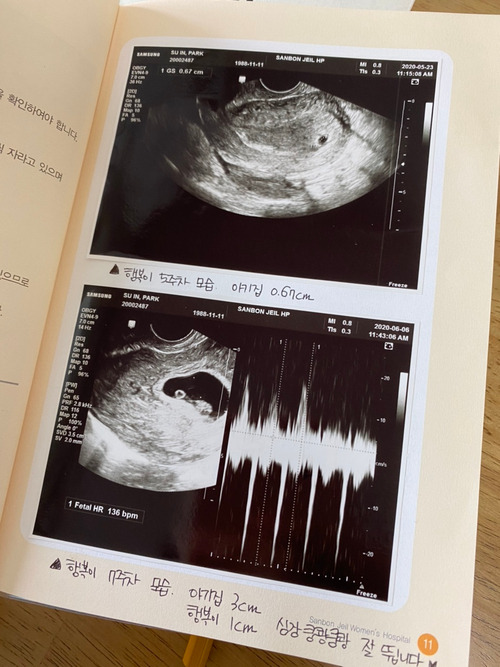

매일 아침 행복이의 상태와 내 몸, 임산부에게 필요한 남편의 조치 등을 알려주는 모아베베 어플을 보는 게 일상이 됐다. 아기집만 봐도 심쿵했는데, 젤리곰 시기를 지나 아가의 모습을 하고 있는 우리 행복이.